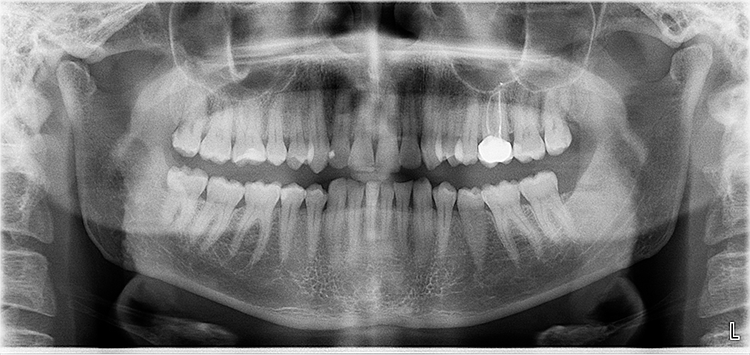

Abb. 3: Repräsentativer Fall von Grad A Typ I. a) Präoperative Ansicht. Röntgenbild der periapikalen Läsion an einem wurzelkanalbehandelten Molaren. Die Höhe des Alveolarknochens zeigt Grad A an. b) Klinische und radiographische Ansicht der Implantatinsertion unter Verwendung einer Einheilscheibe mit großem Durchmesser (6×8 mm). A-PRF wurde um das Implantat und unter der Scheibe platziert. c) Nachuntersuchung nach 5,9 Monaten vor und nach der Zementierung und Aufbereitung. d) Jüngste Nachuntersuchung nach Einsetzen der Prothese